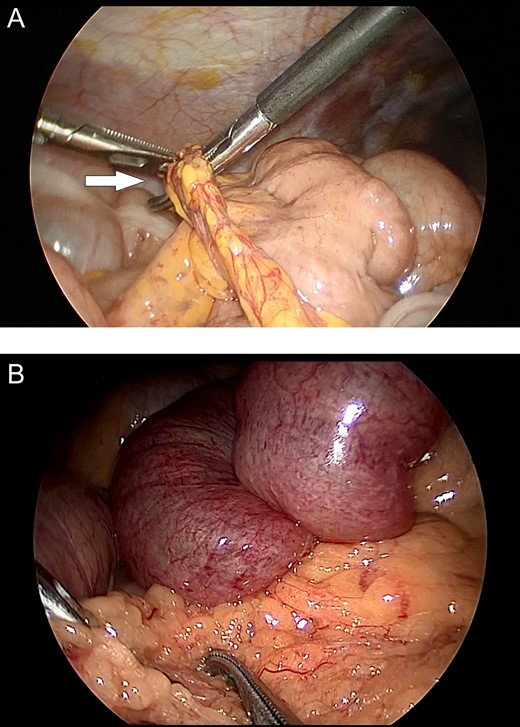

The first patient was a 58-year-old female who presented to our hospital with abdominal pain and vomiting; she had no history of abdominal surgery. Upon performing an examination, her abdomen was soft, with no guarding or rebound tenderness; however, central abdomen palpation revealed tenderness. A laboratory investigation revealed no abnormalities; however, enhanced abdominal computed tomography (CT) revealed intestinal obstruction of the right lower quadrant with the beak sign, indicating the transition zone of SBO (Fig. 1A). Therefore, the patient was diagnosed with strangulation ileus due to the internal hernia. Emergency laparoscopic surgery revealed an incarcerated loop of the small bowel through a greater omental defect (Fig. 2A). The incarcerated small bowel was released; because the ileal segment was viable, bowel resection was deemed unnecessary. The patient was uneventfully discharged on postoperative Day 8.

Intraoperative images. (A) Incarceration of a loop of the small bowel through a defect in the greater omentum (arrow). (B) Small bowel loops appear to be congested and herniate through the greater omentum.